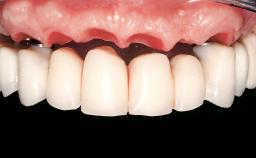

| Defining Characteristics | - |

| Loading Protocol | - |

| Retention | - |

| Esthetic Risk | - |

| Provisional Implant-Supported Prosthesis | - |

| Interim Prosthesis during Healing | - |

| Occlusion/Articulation | - |

| Occlusal Scheme/Issues | - |

| Soft Tissue Contour and Volume | - |